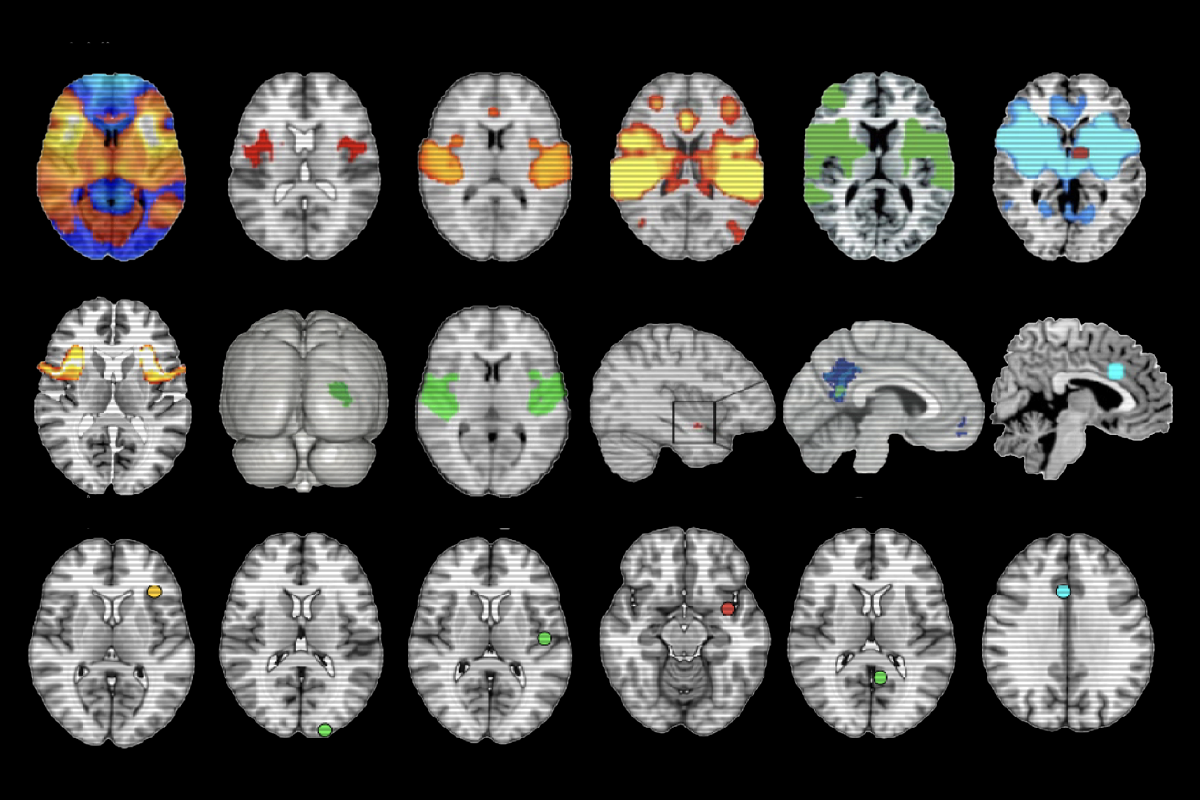

LNM uses the location of brain lesions in various health conditions to infer information about networks of brain activity altered in those conditions. But the January paper claimed the approach produces biased results, and points to largely the same brain networks no matter the condition.

In the Nature Neuroscience critique, Martijn van den Heuvel, professor of computational neuroimaging and brain systems at the Vrije Universiteit Amsterdam, and his colleagues mirror Siddiqi’s early concerns about the high levels of similarity in maps produced by LNM, regardless of the condition being studied. Their mathematical analysis suggested that any condition assessed with LNM would eventually converge to a nearly identical network map, rendering the output meaningless.